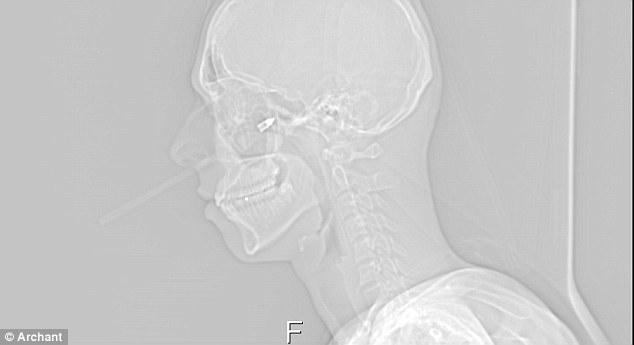

X光片顯示,這支箭插入塔維尼右臉內(nèi)7厘米多深

醫(yī)生檢查后發(fā)現(xiàn),這支箭射入塔維尼的右側(cè)面頰足足3英寸(約合7.6厘米)深,致使他面部肌肉和臉頰骨受損,幸運(yùn)的是并未傷及要害。醫(yī)生稱,這支箭如果再靠上2毫米就會(huì)傷及動(dòng)脈而致命,而如果位置再靠下一些塔維尼將會(huì)喪失說話的能力。